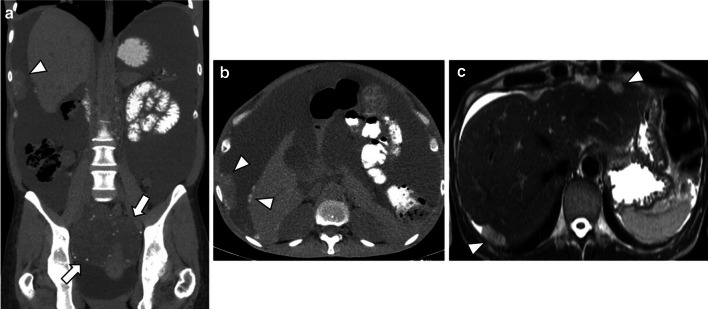

Fluoro-2-deoxy-d-glucose (FDG) PET/CT has a limited role in the primary diagnosis of adnexal masses since false-negative findings have been detected with borderline tumours, mucinous tumours, and other low-grade types of tumours. False-positive results have also been reported with bowel loops, follicular cysts, corpus luteum cysts, and in some benign ovarian tumours [1, 2, 10, 15]. Yet, despite this, FDG-PET/CT can help diagnose and stage advanced disease (stage IV disease), specially when CT is indeterminate [1, 13, 15]. FDG-PET/CT metabolic activity provides disease detection in small metastases or lymph nodes, which can be difficult to characterise only with CT [13, 15] (Fig. 8).

Fig. 8.

Local recurrence of LGSC with peritoneal and lymph node metastases in a 74-year-old female. Axial unenhanced CT images display a large, heterogeneous, mixed tumour in the vaginal dome (arrow) (a) with bilateral inguinal lymph node metastases (arrowheads) (b), both with calcified psammoma bodies. Axial enhanced CT image reveals a peritoneal metastasis in the left hypochondrium peritoneum (arrow) (c). FDG-PET/CT images show a hypermetabolic pelvic lesion (d), bilateral inguinal lymphadenopathies (e) and a left upper hypochondrium peritoneal lesion (f), suggestive of malignancy

Recently, FDG-PET/CT has revealed similar or higher sensitivity (95–97%) and specificity (80–100%) than CT or PET alone to detect recurrent or residual disease [1, 15, 23].

The identification of metabolic activity in infracentimetric metastases and the detection of disease between intestinal loops, especially after surgery, are recognised limitations of PET [1, 15]. Despite this, the anatomical resolution and metabolic activity of FDG-PET/CT outperform those of CT and MRI in detecting lymph nodes recurrent disease and unresectable sites [1, 15].